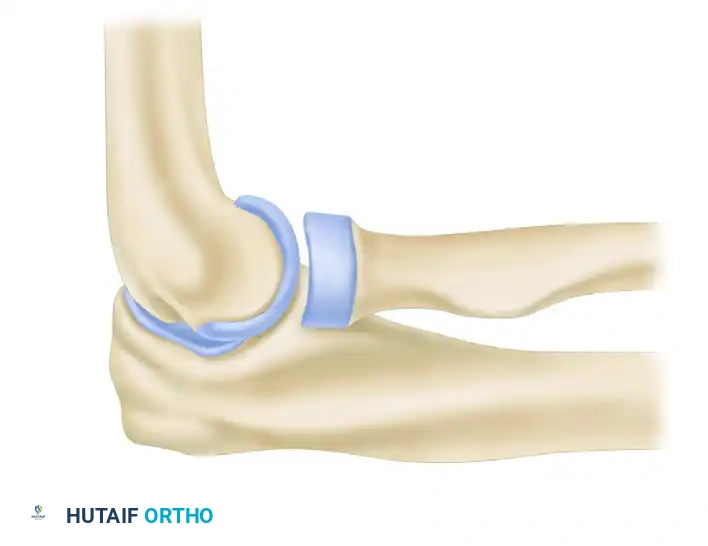

Posterolateral rotatory instability (PLRI) is the most common pattern of chronic elbow instability, typically resulting from a traumatic dislocation or subluxation event that disrupts the lateral collateral ligament (LCL) complex. First comprehensively described by O’Driscoll, Morrey, and Bell, PLRI is characterized by a three-dimensional displacement pattern: the ulna supinates and subluxates posterolaterally away from the trochlea, carrying the radius with it.

The primary pathoanatomic lesion in PLRI is the incompetence or avulsion of the lateral ulnar collateral ligament (LUCL). When conservative management fails and patients experience recurrent symptomatic instability—often described as clicking, locking, or a sensation of the elbow "giving way" during extension, supination, and axial loading—surgical intervention is indicated.

SURGICAL ANATOMY AND BIOMECHANICS

A profound understanding of the lateral ligamentous complex is mandatory for successful reconstruction. The LCL complex consists of four distinct components:

1. Radial Collateral Ligament (RCL): Originates from the lateral epicondyle and blends into the annular ligament.

2. Lateral Ulnar Collateral Ligament (LUCL): The primary restraint to varus and posterolateral rotatory stress. It originates at the lateral epicondyle (sharing a footprint with the RCL) and inserts on the crista supinatoris of the proximal ulna.

3. Annular Ligament: Stabilizes the proximal radioulnar joint.

4. Accessory Lateral Collateral Ligament: Assists in stabilizing the annular ligament during varus stress.

💡 Clinical Pearl: The Isometric Point

The humeral origin of the LUCL is the critical axis point of the ulnohumeral joint. This isometric point lies precisely at the intersection of the anterior humeral line and the radiocapitellar axis. Accurate identification of this point is the most critical step in the procedure; non-isometric graft placement will result in either restricted range of motion or recurrent instability.